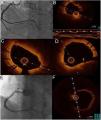

(A and B) Coronary angiography showing the right coronary artery (RCA) with spontaneous dissection from the mid segment and thrombus, resulting in TIMI 1 flow; (C) intravascular ultrasound (IVUS) imaging showing dissection from the posterolateral branch to the mid segment of the RCA with large quantities of thrombus; (D) implantation of three overlapping drug-eluting stents; (E and F) IVUS images showing good stent apposition and expansion and protruding thrombus (arrow).

Since the patient was still in pain during the diagnostic angiography, it was decided to proceed with direct coronary angioplasty assisted by intravascular ultrasound (IVUS) imaging, and three Resolute Onyx™ stents were implanted: one 3.5mm×30mm in the distal segment, one 4mm×38mm proximal to and overlapping the first, and one 4mm×22mm proximal to and overlapping the second. The final result was TIMI 2 flow in the posterior descending and posterolateral arteries. Post-angioplasty control imaging showed good stent apposition and expansion, the presence of intramural hematoma, a degree of protrusion of the in-stent thrombus, and persisting thrombus in the posterolateral artery (Figure 1).

One week after the acute event, coronary angiography was repeated and optical coherence tomography (OCT) was performed, which confirmed good apposition and expansion of the previously implanted stents and the presence of in-stent red thrombus, more clearly visible in the mid-distal part of the vessel, but not significantly obstructing the lumen (Figure 2).